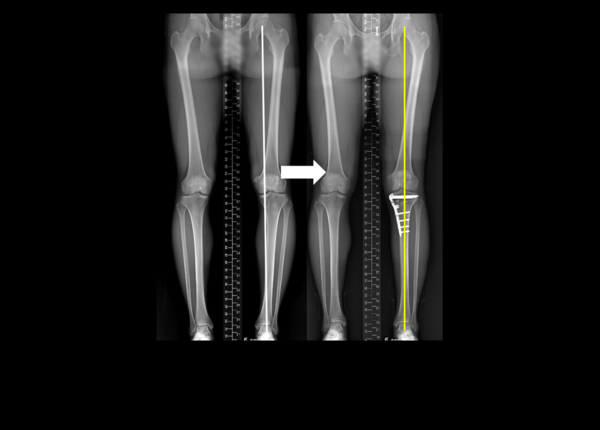

오래 써야 하는 관절 건강을 생각했을 때, 내반 변형(O자 다리 변형)이 3도 이상으로 심한 사람은 내측반월연골판이식술 시 근위경골절골술을 동시에 하는 게 좋은 것으로 확인됐다.

건국대병원은 이 병원 정형외과 이동원 교수가 연구를 통해 내반 변형이 3도 이상인 환자들에게 내측 반월연골판 이식술을 할 때 근위 경골 절골술을 동시에 하면 이식된 반월 연골판의 기능을 증가시킬 수 있다는 것을 확인했다고 16일 발표했다.

이동원 교수는 단독으로 내측 반월연골판이식술을 시행한 환자 22명(내반 변형 평균 1.8도)과 내측 반월연골판이식술과 근위 경골 절골술을 동시에 시행한 환자 20명(내반 변형 평균 4.2도)을 비교했다.

그 결과, 근위 경골 절골술을 동시에 시행한 그룹에서 이식된 반월연골판 탈출 정도가 통계학적으로 유의미하게 적었다. 반월연골판 탈출은 관절 내 반월연골판이 체중 부하로 관절 밖으로 밀려나는 현상으로 3mm 이상 탈출되었을 때 반월연골판 기능이 저하된 것으로 판단한다.